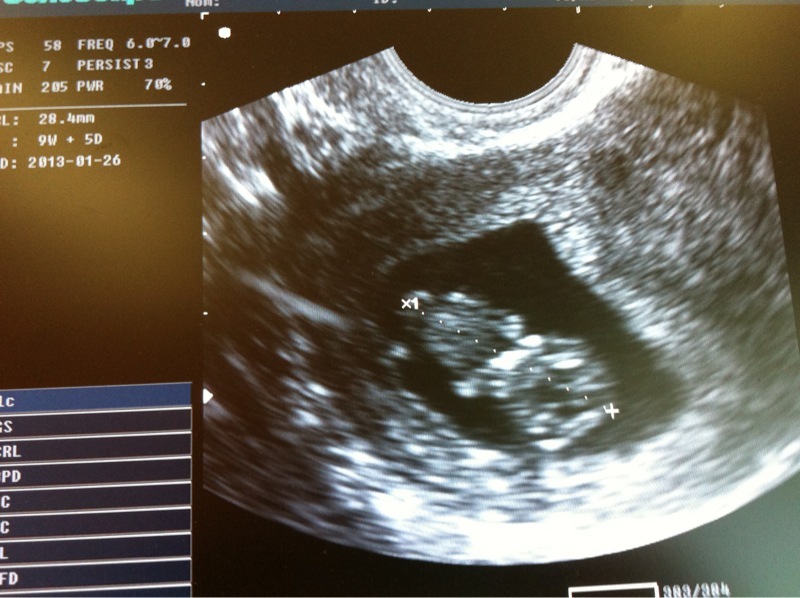

j'espere que j'en aurai une nouvelle et belle toute à l'heure (écho) à partager